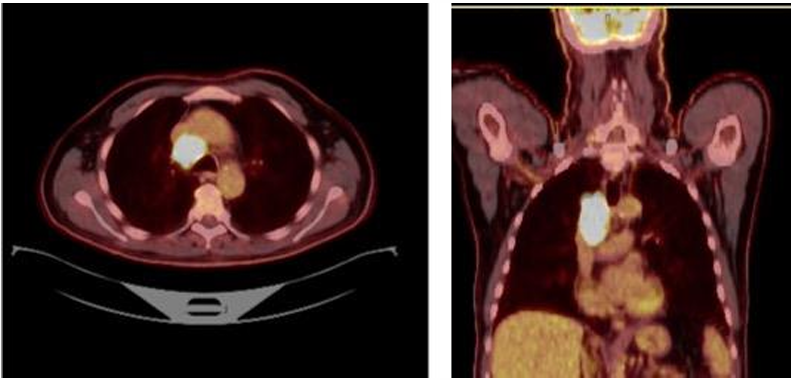

65岁男性,既往重度吸烟史(50包/年),ECOG PS 1分。因肩胛区疼痛入院治疗。胸部CT显示,右肺上叶可见一巨大肿块,最大径达7.3cm。病灶疑似侵犯椎体及胸膜,并伴有可疑的4R组淋巴结肿大。PET/CT显示,原发病灶SUV最高值为17,4R组淋巴结SUV最高值为11。MRI未见转移。临床分期定为cT4N2M0(IIIB期)。

70岁男性,既往重度吸烟史(60包/年)。驱动基因阴性,PD-L1高表达(90%)。临床分期为cT1bN2a(4R组,Bulky/体积巨大)M0(IIIA期)。患者接受3个周期的卡铂+ 培美曲塞+抗PD-1抑制剂新辅助治疗。CT显示,巨大的4R组纵隔淋巴结达到部分缓解(PR)。淋巴结虽然缩小,但新辅助免疫治疗引发的局部炎症和组织纤维化,对后续纵隔淋巴结清扫术的精细度提出更高要求。